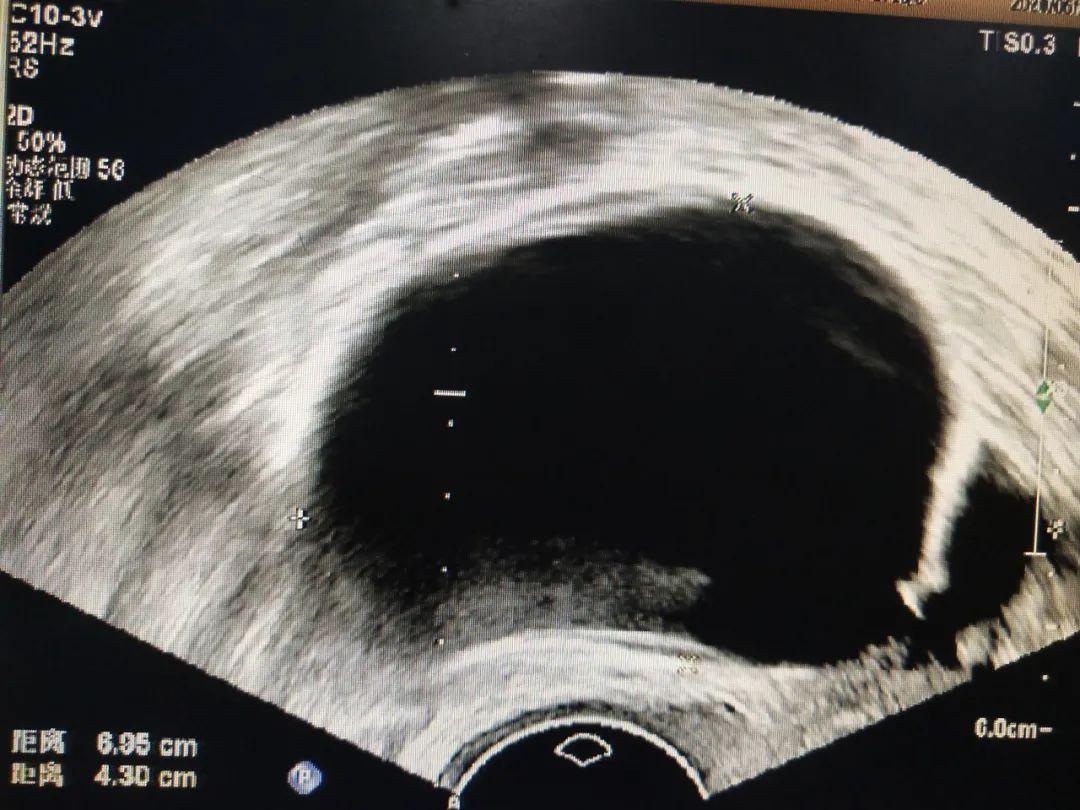

图6经阴道超声巧克力

囊肿抽液硬化术后对比

1、超声引导下肾囊肿、肝囊肿、卵巢囊肿、乳腺囊肿、甲状腺囊肿、淋巴管囊肿等抽吸硬化治疗。